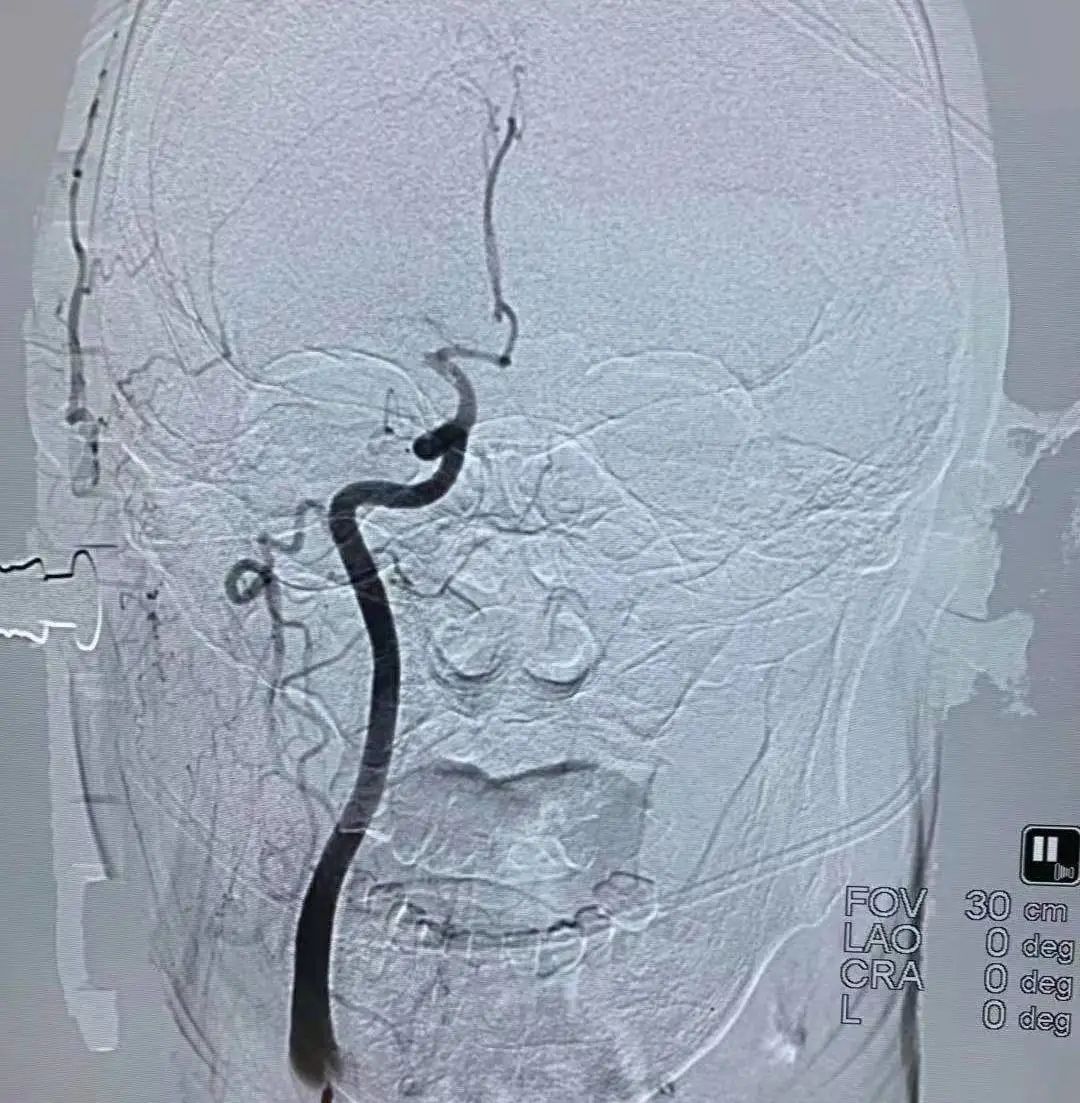

血管内的治疗还包括血管狭窄的治疗,在做头颅磁共振或脑血管造影时,如果发现有血管狭窄,医生就会建议放一个支架,这样就避免了脑梗塞的发生。

近年来,脑血管介入治疗显著提高了闭塞血管的开通率,为静脉溶栓失败和溶栓禁忌的大动脉闭塞患者提供了一种新的治疗选择。但具体诊疗过程中还要因病施治,要根据病人的病情决定什么样的治疗。